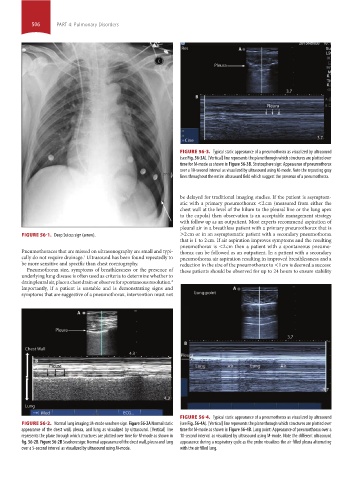

FIGURE 56-4. Typical static appearance of a pneumothorax as visualized by ultrasound

FIGURE 56-2. Normal lung imaging: M-mode seashore sign. Figure 56-2A Normal static (see Fig. 56-4A). [Vertical] line represents the plane through which structures are plotted over

appearance of the chest wall, pleura, and lung as visualized by ultrasound. [Vertical] line time for M-mode as shown in Figure 56-4B. Lung point: Appearance of pneumothorax over a

represents the plane through which structures are plotted over time for M-mode as shown in 10-second interval as visualized by ultrasound using M-mode. Note the different ultrasound

fig. 56-2B. Figure 56-2B Seashore sign: Normal appearance of the chest wall, pleura and lung appearance during a respiratory cycle as the probe visualizes the air filled pleura alternating

over a 5-second interval as visualized by ultrasound using M-mode. with the air filled lung.